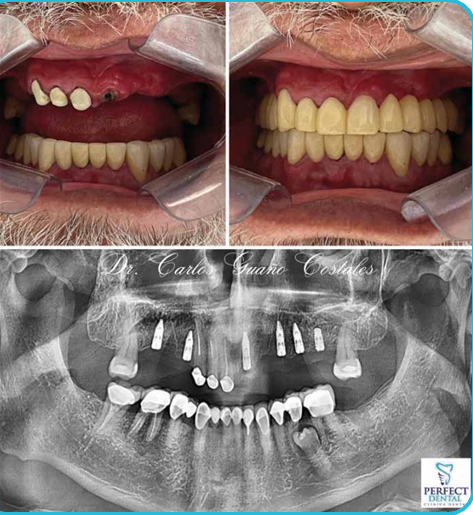

CASO CLÍNICO

Paciente de 60 años acude porque tenia una prótesis sin estabilidad y deseaba tener dientes fijos, así que analizamos su caso y realizamos prótesis fija de porcelana apoyado sobre implantes con excelentes resultados estéticos y funcionales